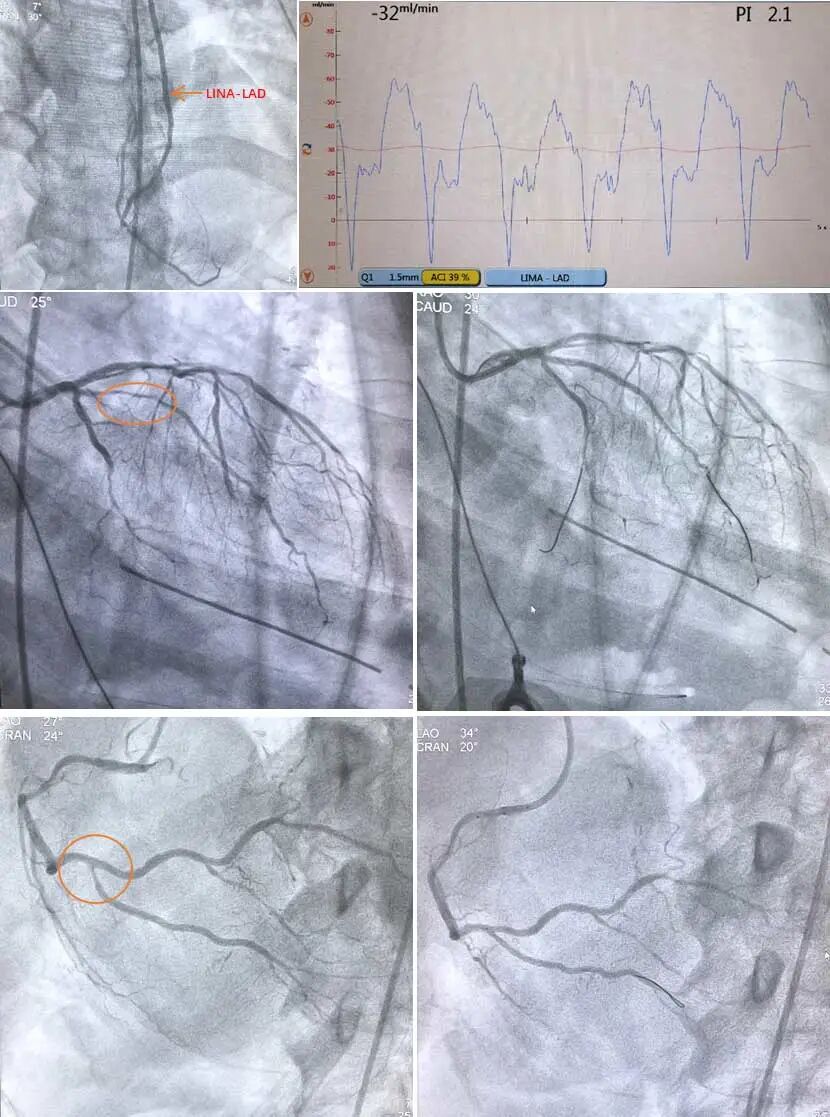

苏丕雄教授团队所进行的“一站式”冠脉杂交手术依托于北京朝阳医院杂交手术室开展。首先,心外科医师完成MIDCAB(经肋间小切口心脏不停跳LAD搭桥),选择左侧第五类间前外侧切口,长约6cm,由高杰医生在胸腔镜辅助下获取LIMA,苏丕雄教授在心脏跳动下直视完成LIMA-LAD搭桥,术中即刻TTFM测量LIMA桥,PI值2.1,血流量32ml/min,波形良好,止血关胸后。

其次,由朝阳医院心脏微创团队张大鹏医生,经左侧股动脉穿刺,首先行LIMA-LAD桥血管造影,血流TIMI 3级,桥血管显示血流吻合口良好。左侧冠脉造影显示中间支近端弥漫狭窄80%以上,LCX细小,给予干预中间支,植入1枚药物涂层支架。右侧冠脉造影显示,RCA主干40-50%弥漫钙化狭窄,PDA开口80%以上狭窄,药物球囊干预PDA开口。手术顺利完成。患者术后血流动力学稳定,完成预计血运重建方案,效果非常满意。